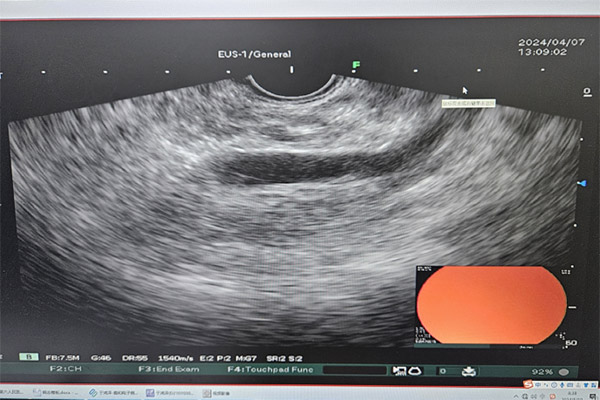

▲病人术前超声内镜检查影像

结合王女士的检查结果,从医三十年的徐进院长认为可以手术切除肿瘤。“您 的肿瘤几乎贴近主胰管,术中主胰管一旦损伤是很难修复的,到时只能被迫切除更多的胰腺。我们利用3D腹腔镜技术来切除肿瘤,视野放大,更加清晰,能大大提 高手术的精确度,降低操作的风险,而且对您的损伤也更小。目前医院设备条件、团队技术水平和临床经验已经完全满足手术的要求。”听了徐进院长的话,王女士 频频点头表示认可。

术前,徐进院长组织普外科、超声科、影像科、麻醉科专家开展MDT,经过充分讨论决定利用3D腹腔镜技术配合腹腔镜超声技术,精准实施胰腺局部切除。腹腔镜超声能精准地对肿瘤进行定位,明确肿瘤与相邻器官、血管的位置关系,3D腹腔镜有效放大手术视野,便于开展精准操作,加上徐进院长极其丰富的临床经验,可以最大限度保护主胰管,减少胰腺的损伤,进而保证胰腺功能和病人术后生活质量。